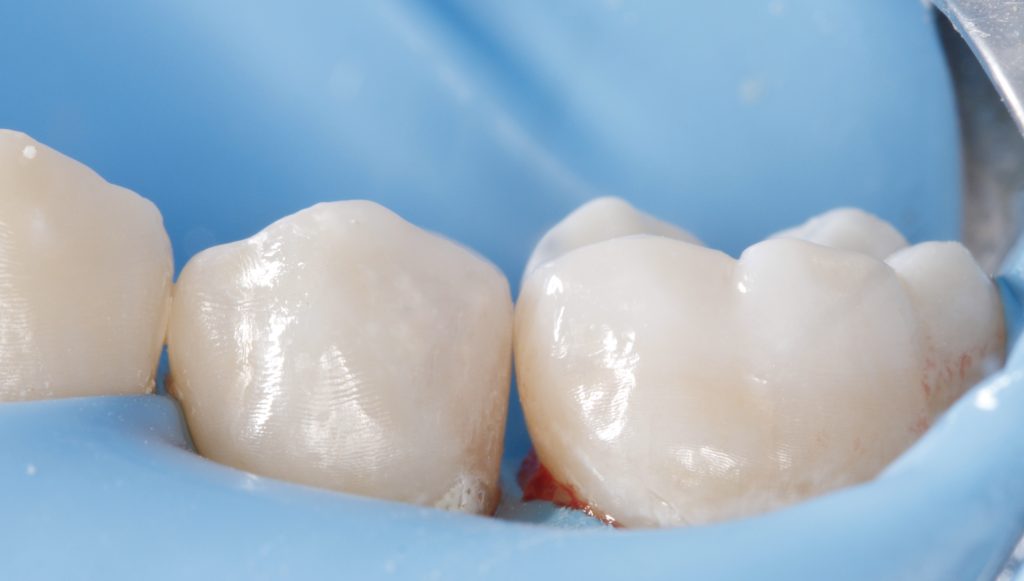

A patient presented with secondary caries under a defective restoration in the maxillary second premolar. The decay extended subgingivally, requiring deep margin management. Rubber dam isolation was applied to ensure a moisture-free environment and protect adjacent tissues during preparation.

- Rubber dam isolation was achieved using a clamp and heavy dam sheet.

- Sandblasting was performed with 30 μm aluminum oxide particles to increase micromechanical retention at the dentin and enamel surfaces (Fig. 1).